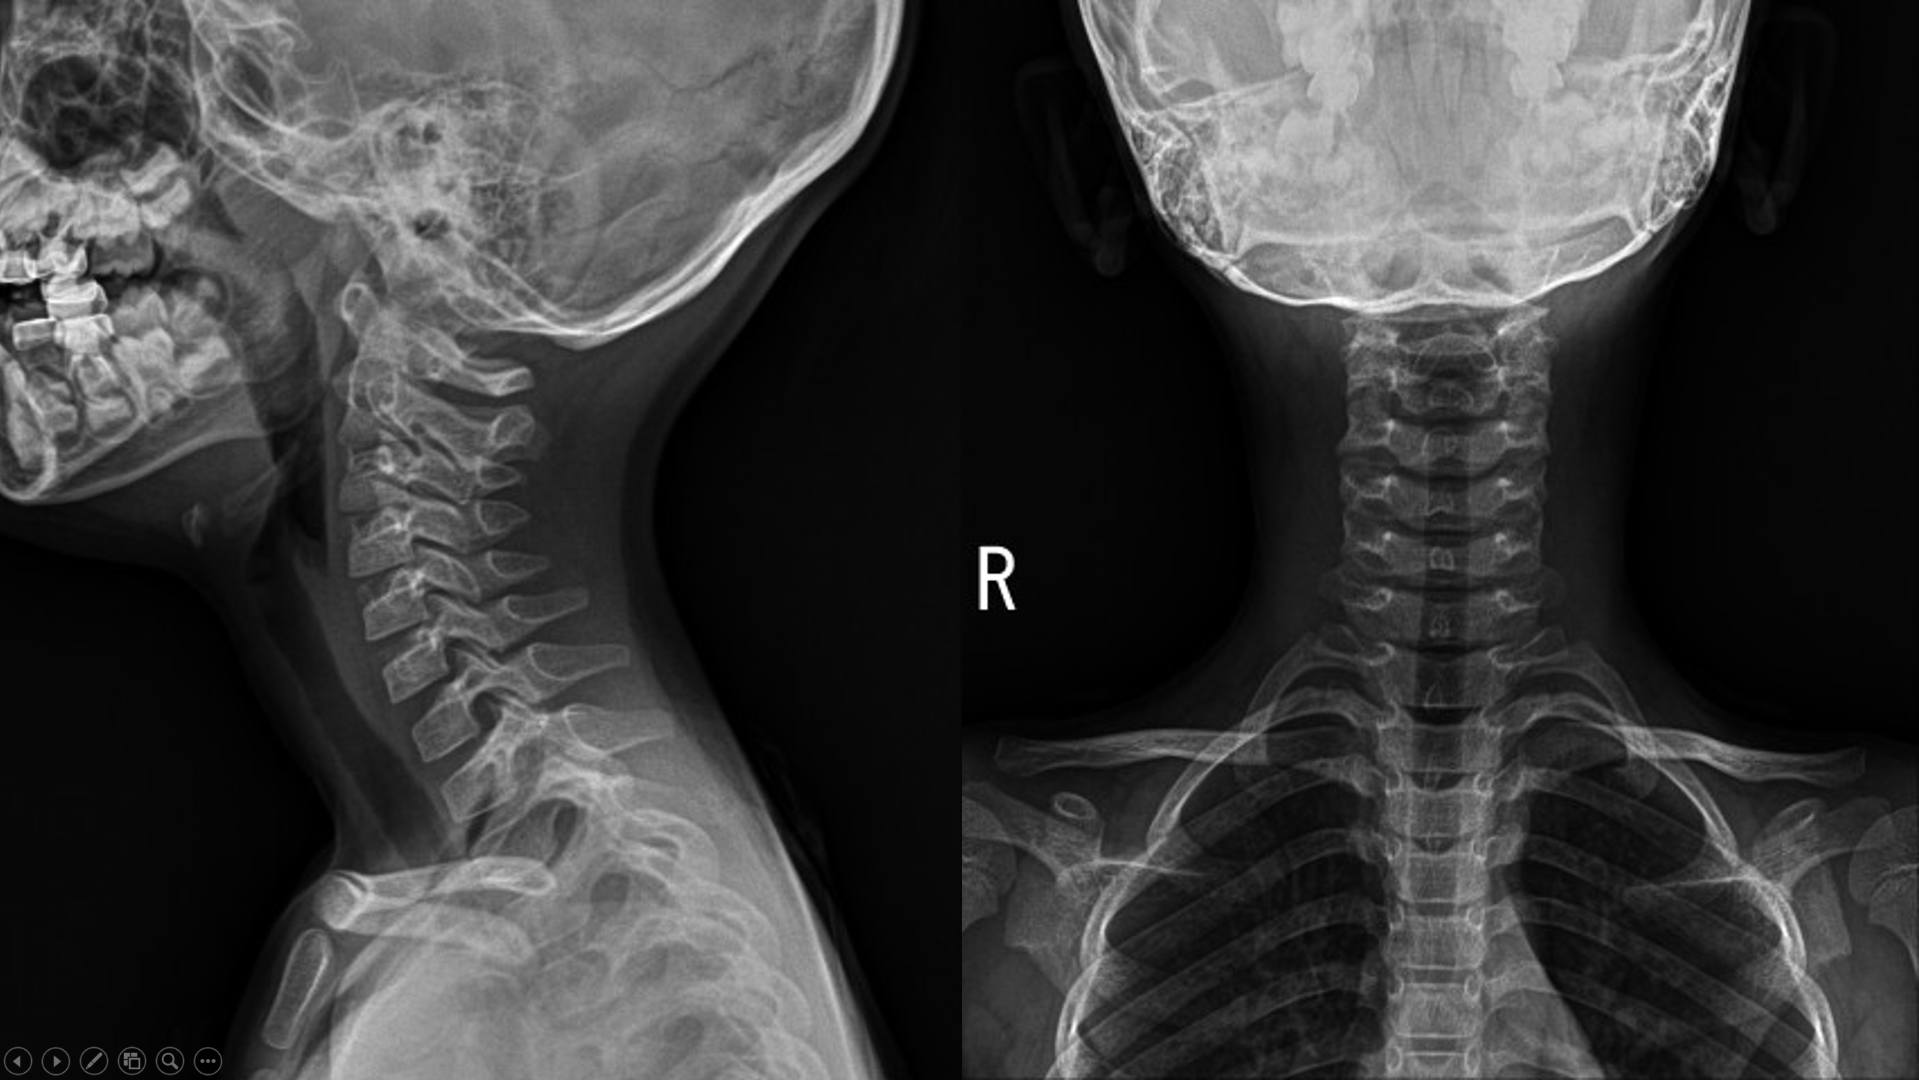

14세 남환

오늘 자고 일어나서 목이 아파 돌리기 힘들다 해서 어머니와 내원

x ray촬영을 해봄

일자목이....

8년 전 6살 때 와서 촬영한 x ray..

비교해서 설명을 해주었는데..

"일단 목이 아파서 일자목으로 촬영될 가능성이 있지만, 일자목으로 보입니다."